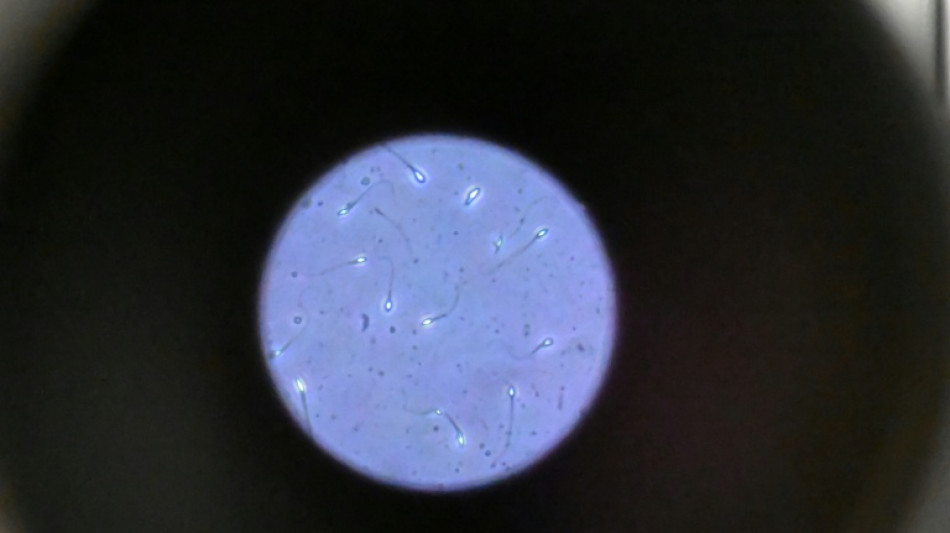

Dans l'espace, les spermatozoïdes ont du mal à trouver leur chemin / Photo: Damien MEYER - AFP/Archives

Dans l'espace, les spermatozoïdes ont du mal à trouver leur chemin vers l'ovule en raison de la microgravité, qui perturbe aussi le développement des embryons, selon une étude publiée jeudi dans Communications Biology.

Les chercheurs ont testé successivement du sperme de souris et humain dans ce dispositif placé dans un appareil en constante rotation pour simuler la microgravité.

Les gamètes ont été environ 50 % moins performants pour naviguer à travers ce parcours que sous la gravité terrestre. Cela équivaut à une baisse de 30% du taux de fécondation réussie, selon les résultats de l'étude.